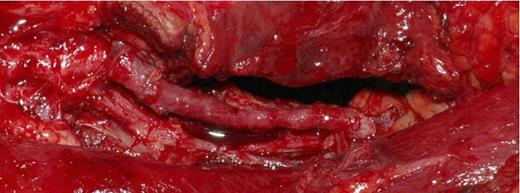

The popliteal artery was explored. (Figure 5) The proximal popliteal artery was found to have a 1cm x 0.5cm wall defect adjacent to the bony exostosis. (Figure 6)The exostosis was excised and the 4cm of diseased artery repaired with end-to-end interpositional long saphenous vein graft. (Figure 7)

Intraoperative Photograph showing the 1cm x 0.5cm defect in the popliteal artery wall caused by the sharp bony exostoses